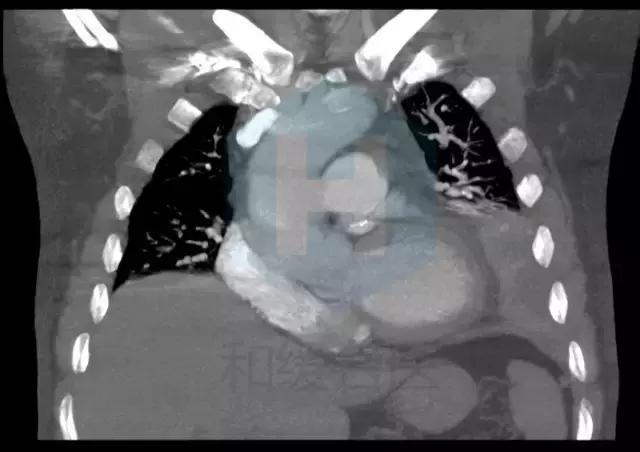

▼影像资料

从CT来看,是比较典型的肺栓塞的表现,应该做肺动脉造影检查。

患者有胸痛,胸闷,1型呼吸衰竭,胸部影像示左下肺为“三角形”肺实变影伴胸腔积液,高度怀疑存在肺栓塞,建议行CTPA检查和肺核素通气/灌注现象检查。同时需排除肺栓塞原因,如肿瘤,自身免疫性疾病等。肺栓塞也会有黄疸和溶血表现。 胸痛特点和表现不符合心绞痛,左侧胸腔积液与左侧肺部病变有关。 患者黄疸考虑为溶血性黄疸,应行查找溶血原因,此外,血红蛋白有下降,便潜血阳性,有同时伴有失血可能,建议查血网织红细胞计数评价贫血情况,应行胃肠镜检查以明确消化道出血原因。 目前低价血症原因考虑不除外副肿瘤综合症可能,关注纠正电解质紊乱。 可视医院条件,建议安排下一步检查:胸部增强CT及CTPA,或肺通气/灌注检查,下肢及深静脉超声,血肿瘤标志物,血网织红细胞计数,自身免疫抗体(ANA,ENA,ANCA)等,胃肠镜检查。 由于目前有消化道出血风险,暂不建议抗凝治疗。密切观察。